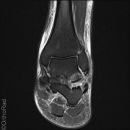

Talus Fraktur